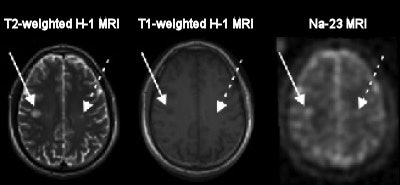

| MR images of a 33-year-old man with early relapsing-remitting multiple sclerosis shows substantial sodium accumulation in two T2 lesions with two different signal intensity patterns at T1-weighted imaging. One lesion was hypointense (solid arrows) and one was isointense (dashed arrows) to normal-appearing white matter on T1- weighted image. Images courtesy of Radiology. |

In addition, MR images showed that the amount of sodium accumulation in gray matter associated with motor skills directly correlated with the degree of disability exhibited by relapsing-remitting MS patients.